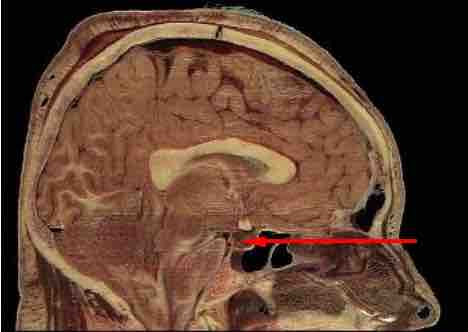

Pituitary location

The location of pituitary gland in the human brain.